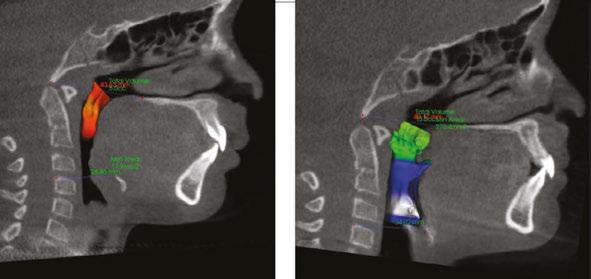

A pediatric-patient dedicated Sleep Medicine laboratory setting is difficult or impossible to find, setting aside what is considered the diagnostic gold standard, overnight PSG. Most screening questionnaires can be valuable as SRBD morbidity assessment tools and reliable for predicting increased risk. They are based solely upon identifying SRBD behavioral phenotypes known to be associated with suboptimal sleep hygiene (e.g., snoring, teeth grinding/bruxism, excessive bodily movements). The Sleep Clinical Record (SCR)15 is an exception because it relies on not only behavioral morbidity traits, but also some physical morbidity traits such as constrictive/retrusive and retrognathic jaw maldevelopments,16 which are known to be associated comorbidities with SRBD.17 Most of these physical traits can be classified as malocclusion phenotypes and generally are located within the interconnected craniofacial respiratory complex (CFRC)18 (Fig. 1) which was foreshadowed by Dr. LeRoy Johnson in the opening paragraph of

this review: ‘The face has evolved with the functions of mastication and respiration.’- L.J. 1921.

While the SCR goes further than most other screening assessment tools towards identification of some CFRC/SRBD co-morbidities, it is limited in its comprehensiveness. Ideally, in addition to screening for birth/perinatal history risk factors, such as pre-term birth,19,20 clinicians should have validated screening tools for identifying behavioral comorbidity traits, and for identification of physical risk phenotypes of the CFRC. The CHICAGO HEARTS screening tool combines these survey areas. (Fig. 2).

In a lecture held in 2018 at Boston University entitled ‘Sleep Disordered Breathing/Obstructive Sleep Apnea Symposium’,21 a new screening tool called C.H.I.C.A.G.O. H.E.A.R.T.S. (C.H.) had been introduced as potentially becoming the first validated screening device specifically designed to identify CFRC physical traits that can often be comorbid with SRBD. Several of these traits are listed within the C.H. acronym (Fig. 2). For instance, under the first letter ‘C’ are listed: Crossbite 22,23 Fig. 3 and Crowded Pharynx;24,25 ‘H’: Hyper-divergent growth (Fig. 4),16 Hypertrophic tonsils and/or adenoids;26,27 ‘I’: Incompetent lips;28 ‘C’: Constricted arches (Fig. 5);23,29,30 ‘A’: Airway anatomy (Fig. 6);22,31 ‘G’: Grinding teeth (bruxism)32 and Gonial angle excess;33 ‘O’: Overweight child34 and Obtuse nose-lip angle( NLA);35 ‘H’: Highly-vaulted palate;36 ‘E’: Ezcema-atopia37 and Eye appearance-venous pooling38 and scleral show;39 ‘A’: Anterior open-bite

(Fig. 8):40 ‘R’: Retrognathia (Fig. 9) (mandible16 and/or maxilla);41 ‘T’: Tongue posture,42 tie (tether),43,44 scalloping;45 ‘S’: Septal deviation46 and night Sweats (diaphoresis).47